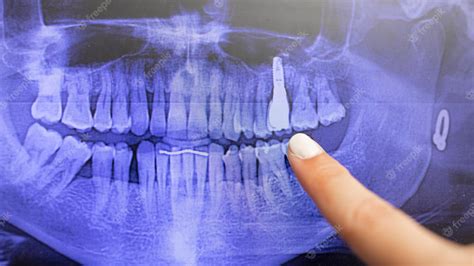

Once the image is captured, it is processed digitally and appears almost instantly on the dentist's monitor. The panoramic Xray teeth view allows your dentist to zoom in and out, highlighting specific areas of interest. You might see lines or shadows that seem confusing, but your dentist will walk you through the image, pointing out the health of your bone structure and the orientation of your tooth roots. This visual aid is an excellent educational tool, as it allows you to see exactly what the dentist sees, making it easier to understand the necessity of recommended treatments.

For example, if you have wisdom teeth, the dentist will point out their proximity to the inferior alveolar nerve—a crucial piece of information for a safe extraction. If you are experiencing jaw popping or clicking, the dentist will show you the TMJ condyles to ensure they are moving smoothly within the joint socket.